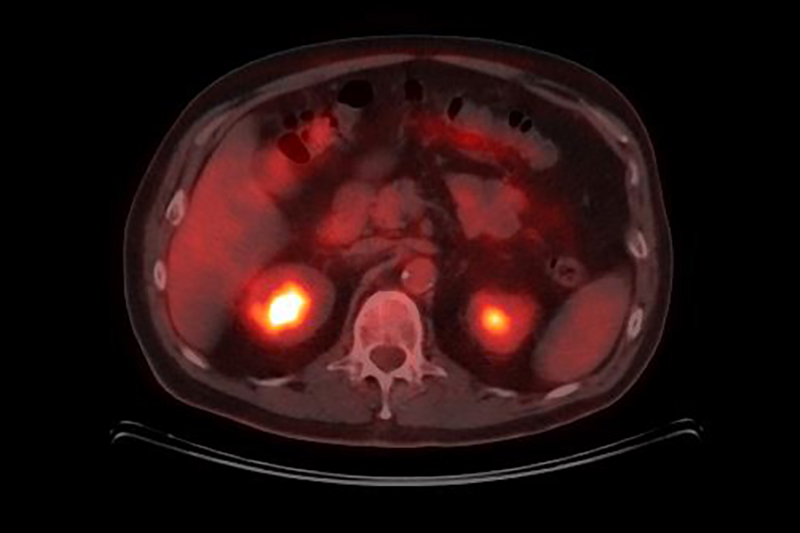

Cada vez hay más pruebas de que cancer risk and obesidad están directamente relacionados. Las células grasas tienen varios efectos sobre los reguladores del crecimiento celular. Los altos niveles de insulina e IGF-1 pueden promover el desarrollo de cánceres de colon, riñón y próstata. El tejido adiposo también produce cantidades excesivas de estrógenos que se han asociado con el cáncer de endometrio, ovario y seno.